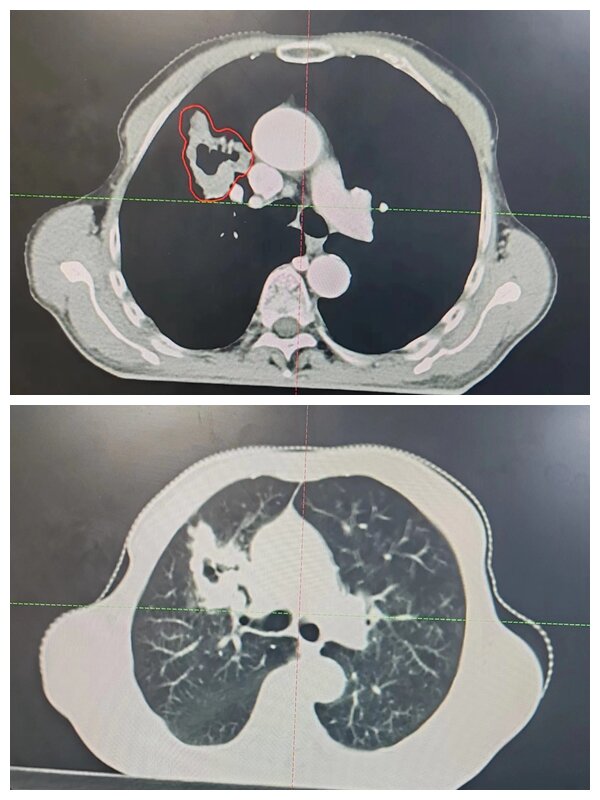

放療中

為盡可能保護(hù)好患者的心肺功能,使正常組織少受射線影響,放療科團(tuán)隊(duì)嚴(yán)格控制脊髓、雙肺、心臟等器官受量,從CT定位到精確設(shè)計(jì)放療靶區(qū),從放療時(shí)間安排到每一次的擺位治療,從精心護(hù)理到營(yíng)養(yǎng)支持干預(yù),每一個(gè)環(huán)節(jié)醫(yī)護(hù)人員都通力協(xié)作,盡最大努力為患者的健康保駕護(hù)航,治療期間患者耐受性良好,未出現(xiàn)嚴(yán)重不良反應(yīng)。經(jīng)過(guò)三周的治療,患者癥狀明顯緩解,病情得到有效控制。